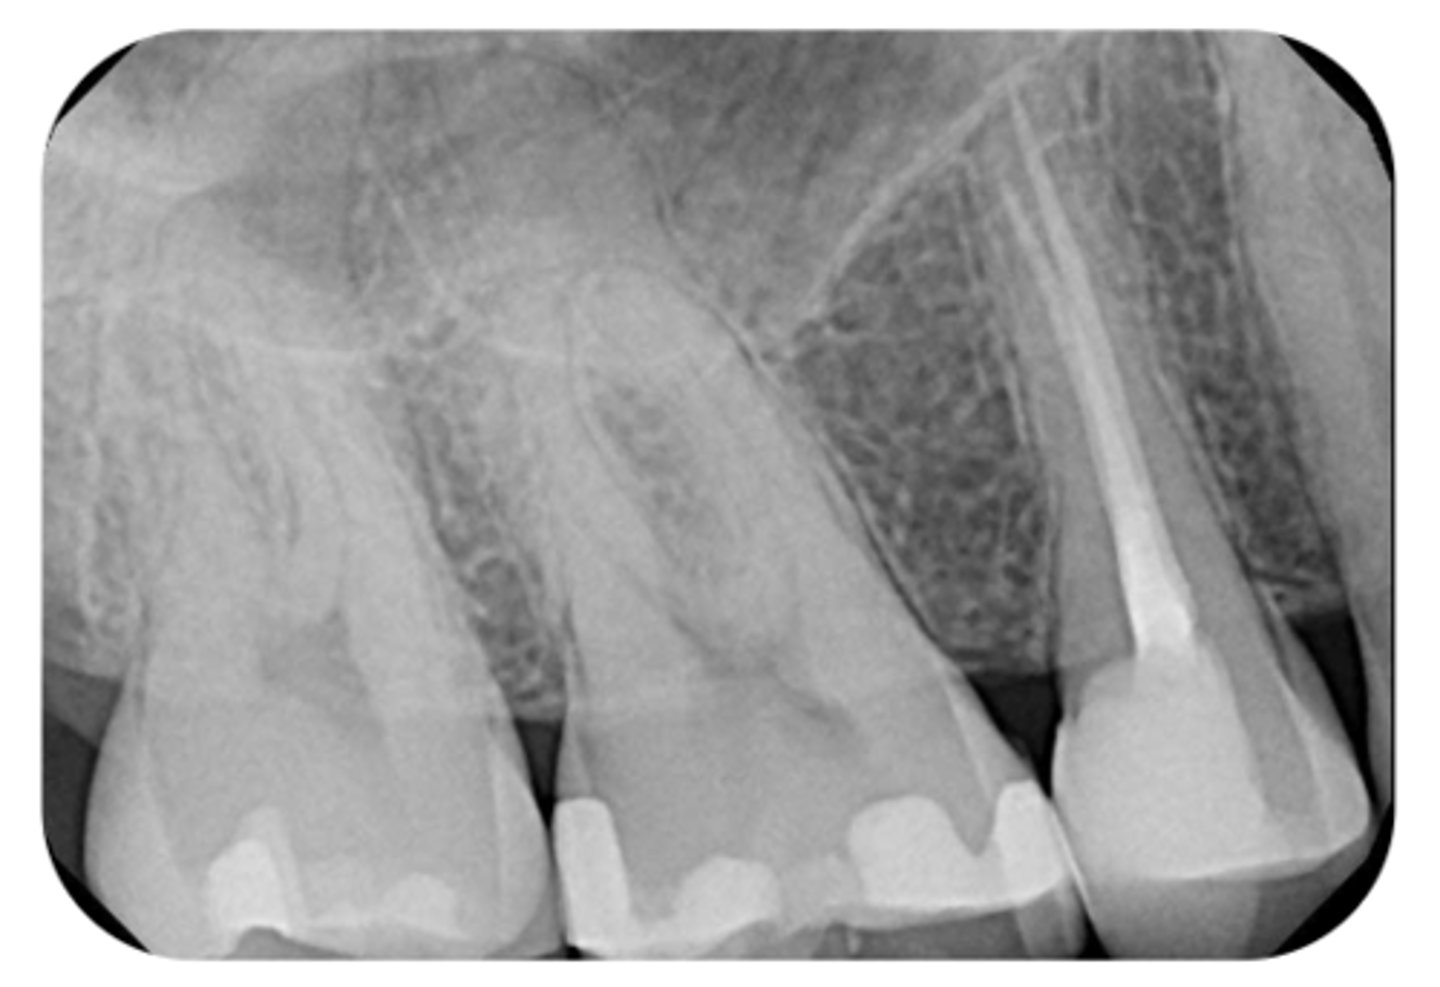

What are the radiographic findings on #13?

- Crown

- Post